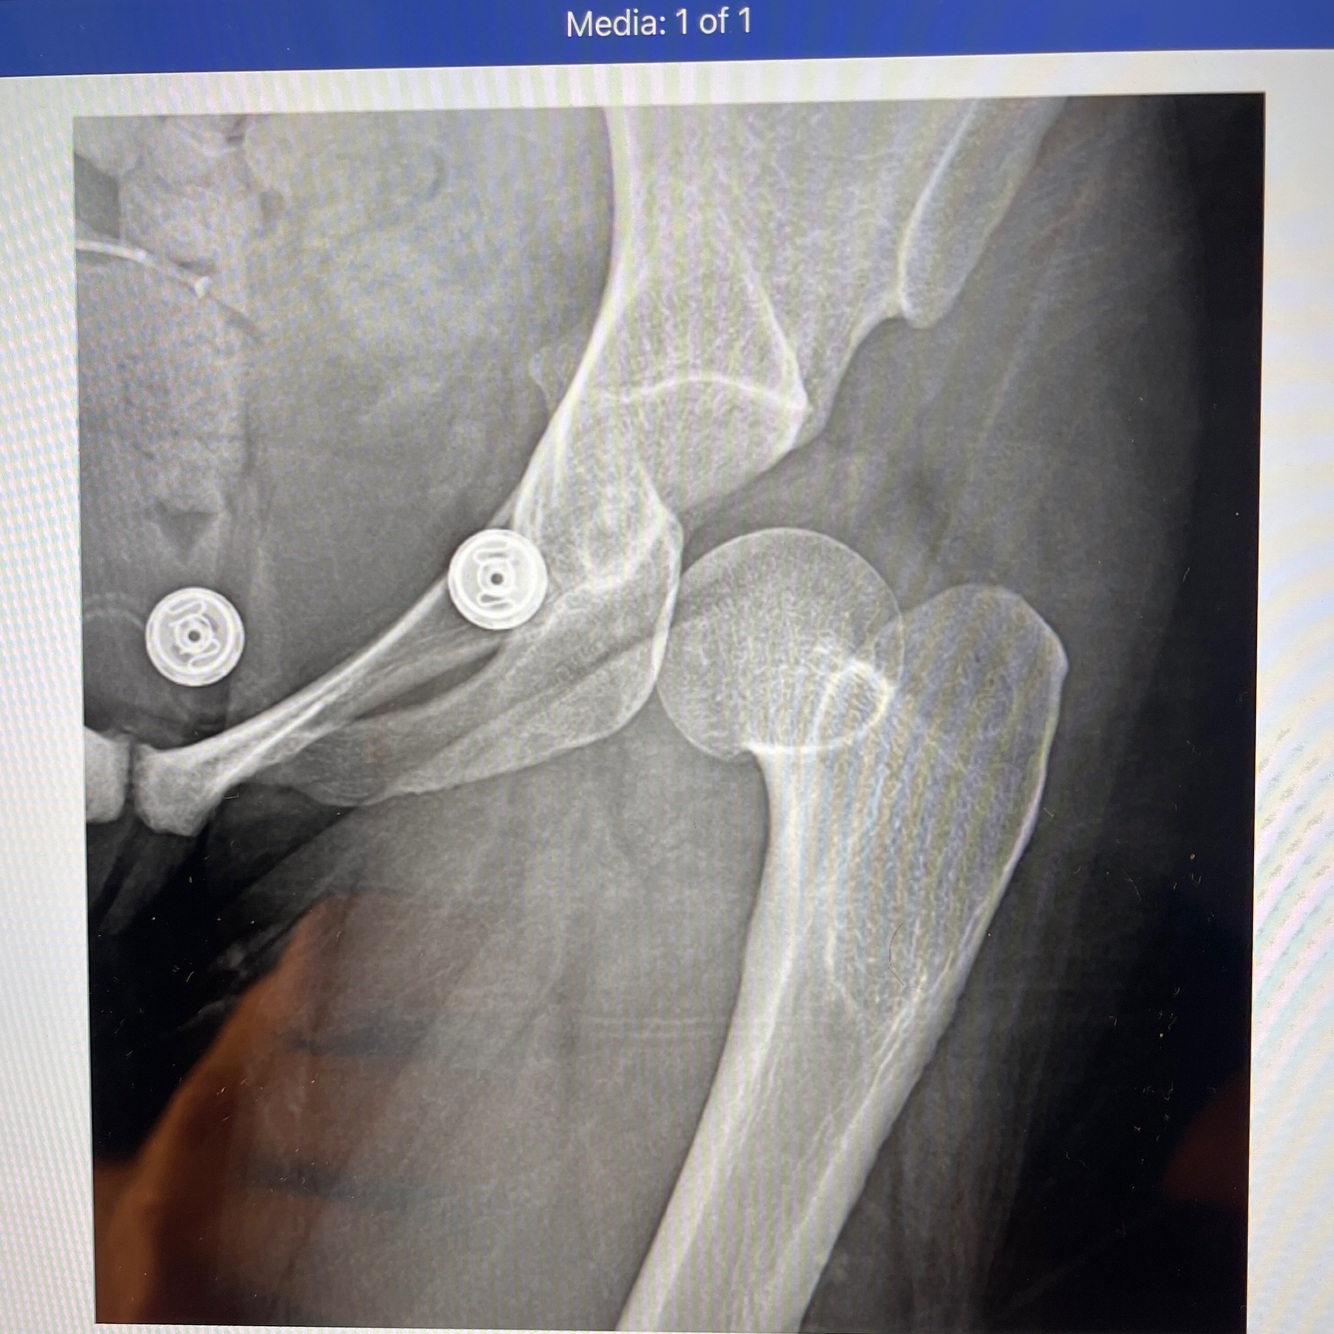

A

How well did you know this?